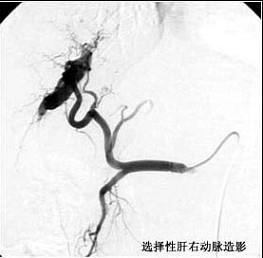

问题 诊断直径小于2cm的肝癌,最好的定位方法是 ( )

选项 A、胆道造影术 B、选择性腹腔动脉造影术 C、同位素肝扫描 D、B型超声波检查 E、肝穿刺术

答案 B